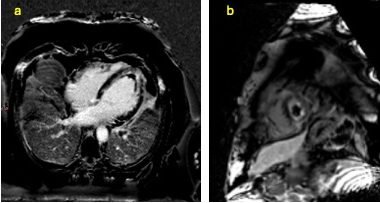

A 49-year-old male with no prior comorbidities presented to the emergency room (ER) with a 7-day history of fever, cough and shortness of breath. On admission, the patient had a blood pressure of 80/56 mmHg, a heart rate of 120 bpm, a respiratory rate of 36/minute, elevated jugular venous pressure, clear lung fields and muffled heart sounds on auscultation. An electrocardiogram was done, which showed sinus tachycardia with low-voltage QRS complexes. A screening bedside echocardiogram showed a large pericardial effusion (maximum thickness of 28 mm) with right ventricular diastolic collapse, suggestive of tamponade physiology. A bedside echocardiography-guided pericardiocentesis was attempted in the ER. Initially, 15 ml of haemorrhagic fluid was drained, after which no further fluid was drained. Cardiology consultation was obtained, and the patient was transferred to the cardiac catheterization laboratory.